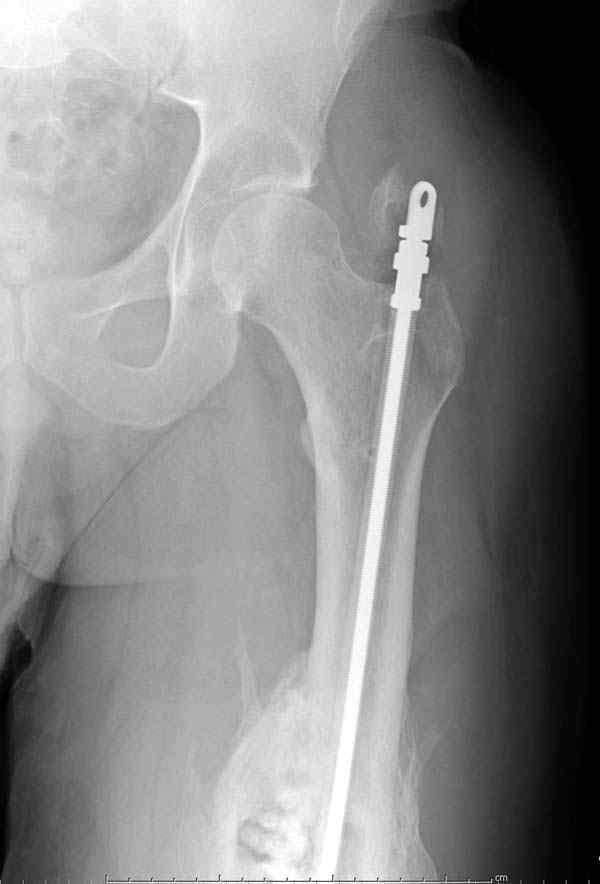

Через 4,5 лет после травмы выявлены рентгенологические признаки консолидации перелома, признаки хронического остеомиелита купировались. Аппарат был демонтирован. Пациент продолжил ходьбу с дозированной нагрузкой на конечность при помощи костылей. Через 2 месяца начал ходить при помощи трости. Однако, еще через 2 месяца отметил появление свищей на бедре с гнойным отделяемым и укорочение длины конечности. При осмотре в январе 2007 г.: пациент ходит при помощи костылей без опоры на левую нижнюю конечность, на бедре имеются множественные рубцы, на наружной поверхности сегмента в верхней и нижней третях имеются два свищевых хода со скудным серозно-гнойным отделяемым; отечности тканей конечности нет, пальпация безболезненная, отмечается укорочение длины конечности на 5 см, патологическая подвижность не определяется, имеется стойкая разгибательная контрактура коленного сустава (разгибание - 180 гр, сгибание - 170 гр), признаков нарушения кровоснабжения и иннервации тканей конечности нет. Температура тела нормальная. В общих анализах крови и мочи отклонений от нормы нет. [image 06,07, 08 (стрелками отмечены свищевые раны, 09, 10]Дорогие коллеги, я уверен, что у многих из вас после знакомства с данным клиническим наблюдением появится множество вопросов, касающихся уже проведенного лечения (особенно, сроков и способов). Сразу оговорюсь - я не смогу правильно ответить на многие вопросы (особенно касающиеся предшествующего периода лечения). Прошу вас, конечно по возможности, сосредоточить внимание не на разборе допущенных ошибок (проведенного лечения), а помочь добрым советом относительно тактики наших дальнейших действий. Наверное, кто-то располагает бесценным опытом лечения подобной патологии.

желаю только успеха и чтоб все трудности которые будут преодолел.

Прикрепляю пример замещения дефекта бедра 20 см, после резекции по поводу опухоли, эндопротеза Сиваша, вялотекущего остеомиелита со свищами в течении 3 лет. Получилось хорошо и всего за 6 месяцев в аппарате. Колена не было. У Вас случай сложнее. Это было в 1998г. Я работал в ЦИТО и у меня было 4 больных, я занимался им с утра до ночи. Сейчас 60 больных и операций в нашем отделении 25-30 в неделю.Если могу чем помочь - нет проблем.